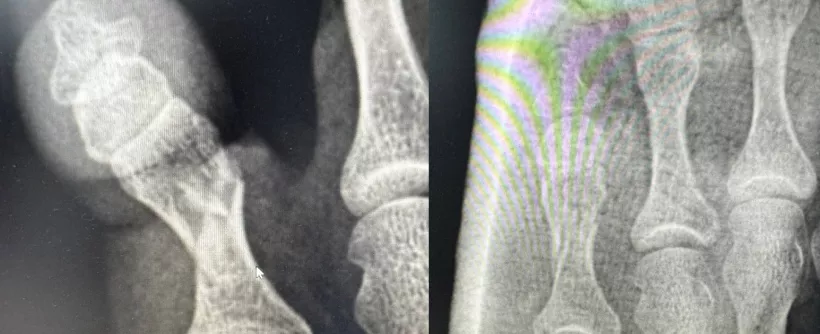

Осмотр и рентгенография позволили поставить диагноз — оскольчатый перелом проксимальной фаланги 5-го пальца. Иван Александрович выполнил репозицию (сопоставление) отломков кости и иммобилизацию стопы гипсовой лангетой. Контрольная рентгенограмма после процедуры позволила оценить результат и убедиться в восстановлении фрагментов. Пациентка довольная уехала домой.

Перелом пятого пальца левой стопы (1) и после репозиции кости и иммобилизации гипсовой лангетой